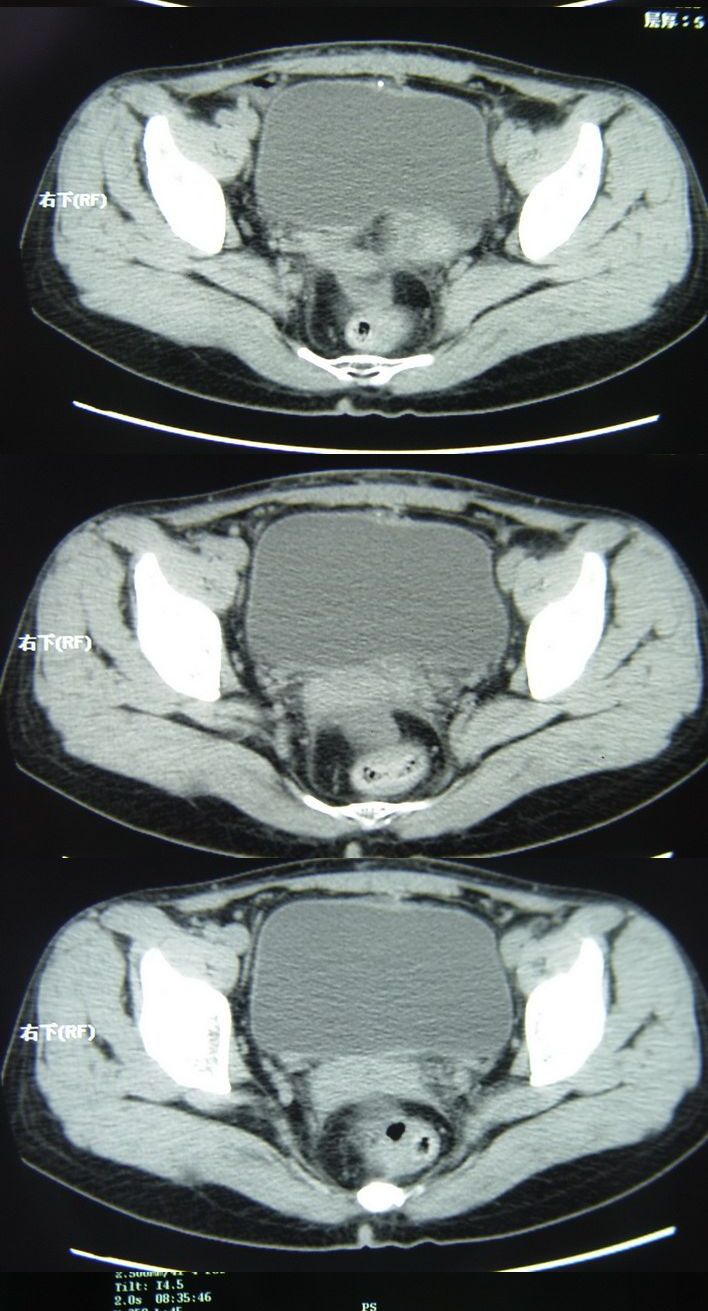

以下是今天的增强片,大家可以看看:

该病人今天做了增强,右侧髂骨病灶明显强化。

据患者家属提示,曾在某医院检查说是卵巢有问题,患者这一次做ct增强,主要目的是排除卵巢病变,担心骨转移

右侧髂后上棘局限性囊状骨质破坏,大部分界清,似见轻度硬化边,内无分格及钙化,病灶上部局部显示模糊。考虑;骨巨细胞瘤可能大,不除外abc。另可见子宫肌瘤术后子宫缺如。

临床和影像学表现:女性患者46岁,有子宫肌瘤手术病史。影像所见可见残余宫颈部分,左右附件未见新生物;右髂骨翼后端囊状膨胀性骨破坏,囊性部分感觉有强化(楼主标上增强前后的ct值就很好了),未见明确的液—液平面,周边硬化不明显或轻度硬化。

分析:患者年龄46岁,没有明确外伤病史,病变呈膨胀性骨破坏,囊性部分未见明确的液—液平面,周边硬化不明显。综合分析该病例比较符合骨巨细胞瘤,不太符合动脉瘤样骨囊肿。

诊断:1、首先考虑骨巨细胞瘤;2子宫肌瘤术后改变